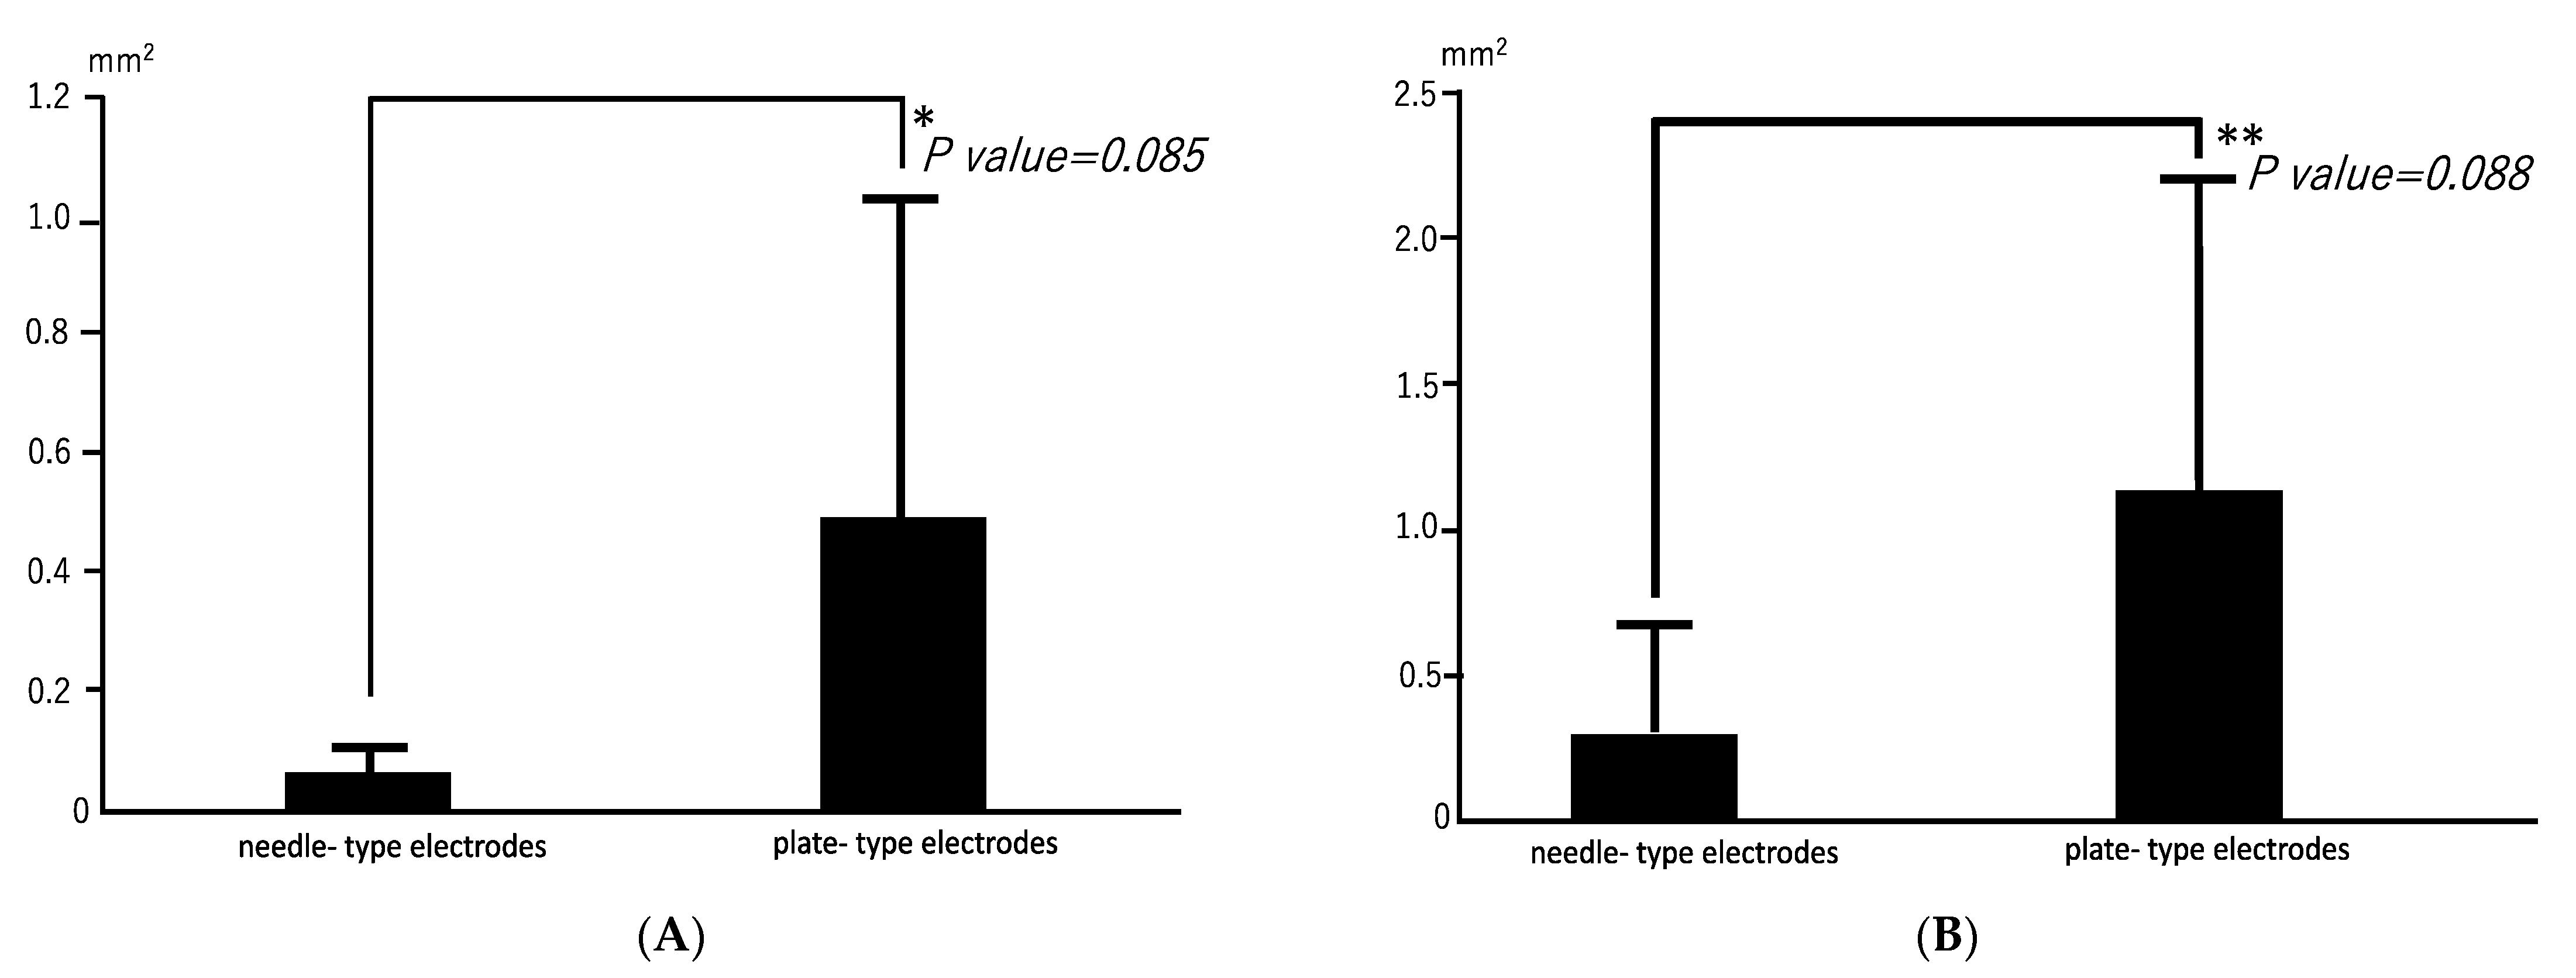

3.1. Radiographic Findings